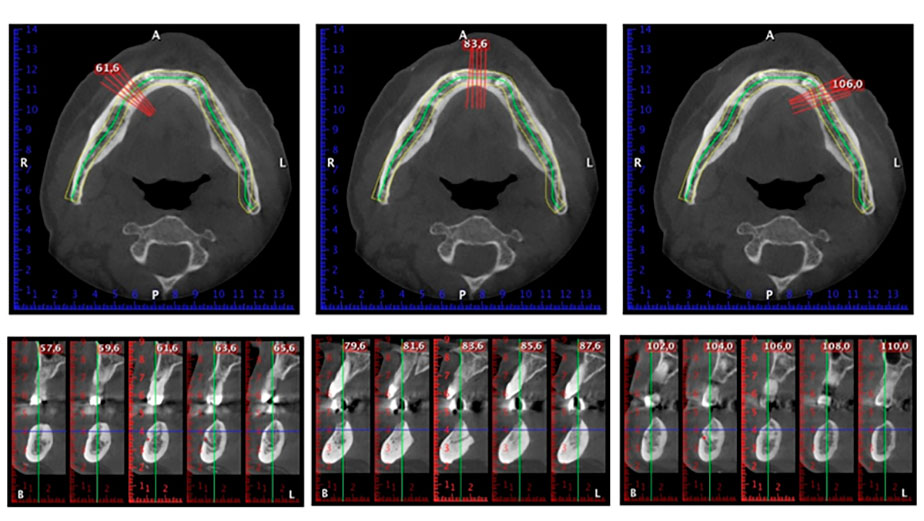

След изчакване на необходимото време за осеоинтеграция, финалният отпечатък на имплантите е свален и следователно е изработена финалната протеза (Фиг. 19 и 20). В този момент, лекарят по дентална медицина и пациентът могат да обсъдят дали да използват керамични или пластмасови фасети и циркониева или метална рамка. В този случай, екипът на д-р Паску избира пластмасови фасети, имайки предвид неясната прогноза относно частичното обеззъбяване в челюстта и фактът, че зъб 24 е прорастнал. Този вид протеза обикновено е по-лесна за адаптиране и впоследствие може да бъде променяна спрямо новата ситуация в челюстта.

Осеоинтеграция

Фиг. 19

Импланти

Фиг. 20